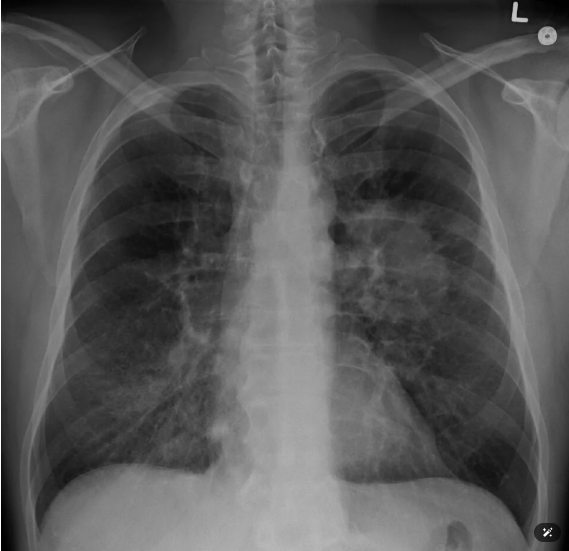

폐결절은 폐 속에 동그랗거나 불규칙한 음영이 잡힌 상태를 가리킵니다. X-선만으로는 찾기 어려웠으나 저선량 CT 보급 덕분에 6 mm 남짓한 미세 결절도 놓치지 않습니다. 크기가 3 cm를 넘으면 ‘폐 종괴’로 분류해 접근이 달라지므로, 3 cm 미만인지가 첫 번째 판단 기준입니다.